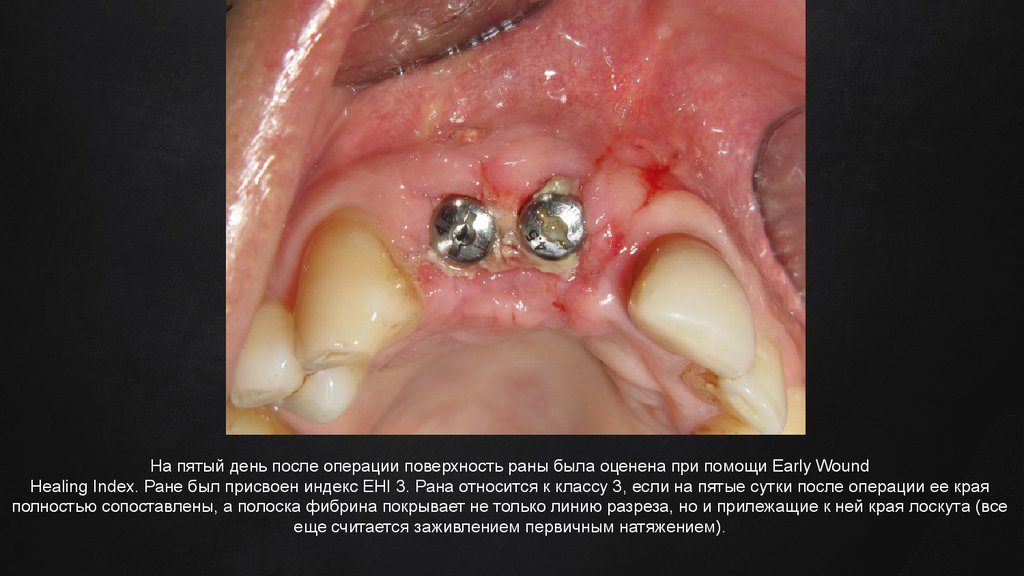

На пятый день после операции поверхность раны была оценена при помощи Early Wound Healing Index. Ране был присвоен индекс EHI

3. Рана относится к классу 3, если на пятые сутки после операции ее края полностью сопоставлены, а полоска фибрина покрывает не

только линию разреза, но и прилежащие к ней края лоскута (все еще считается заживлением первичным натяжением).